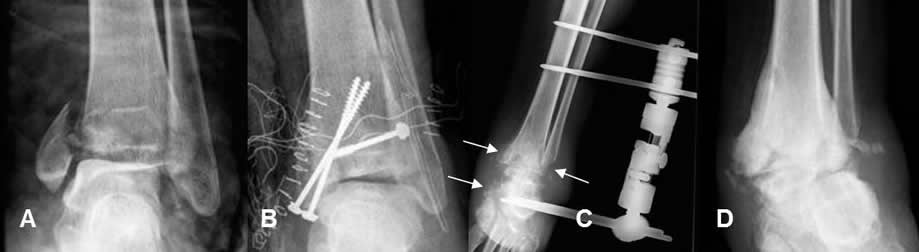

Fig 113 A. Infección del material.

A: Rx AP. Fractura desplazada del maleolo interno.

B: Rx AP. Reducción y fijación con tornillos.

C: Rx AP. Edema de tejidos blandos en el tobillo y osteolisis del calcáneo y ambos maleolos por osteomielitis, lo cual obliga a retirar el material y coloca tutor externo.

D: Rx AP. Como secuela queda artropatía neuropática hipertrófica y artrosis de la articulación.